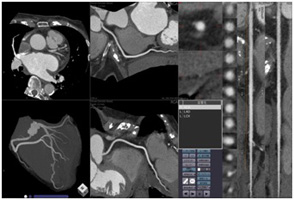

心臓CT検査

常に動いている心臓を正確に撮影するために、心臓の動きを一時的に遅くさせる薬を使用することがあります。薬が効き始めるのに一時間近くかかりますので、検査時間の一時間前に来院し、中央処置室(当院内科の横)へお越しください。

検査中は、心電図を測定しますので軽装になっていただきます。

息止めが非常に大切な検査ですので、検査中何度も息止めの練習を行います(息止めは約10秒)

ただし、どうしても息止めがうまくいかない場合は検査を中止することがあります。

検査後30分ほど安静にしていただき、異常がなければ帰宅していただきます。